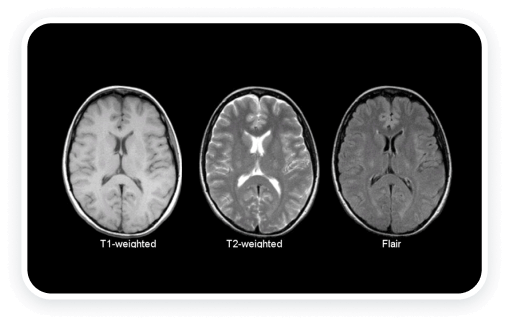

The MRI scans showed that the higher stress levels in the Amygdala of poorer people prevented them from seeing opportunities for wealth and abundance in their lives. It stops them from taking action.

Dr Roberts's MRI scans showed wealthy people had a group of neurons in their Amygdala in the ‘on position.’

The Amygdala is the part of the brain that controls stress and anxiety.

Wealthy people had what Dr. Roberts and his team metaphorically called a ‘Wealth Circuit’ turned on in their Amygdala.